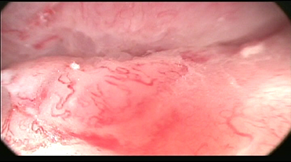

The vaginal image prior to treatment shows a vaginal fundus with a large ulcer with telangiectasias and mucositis (Image 3), and after the 4th treatment a vagina is found with frank reduction in the size of the ulcer, mucositis in resolution and absence of telangiectasias (Image 4).

Image 3 Vagina prior treatment.

Image 4 Vagina after fourth treatment.